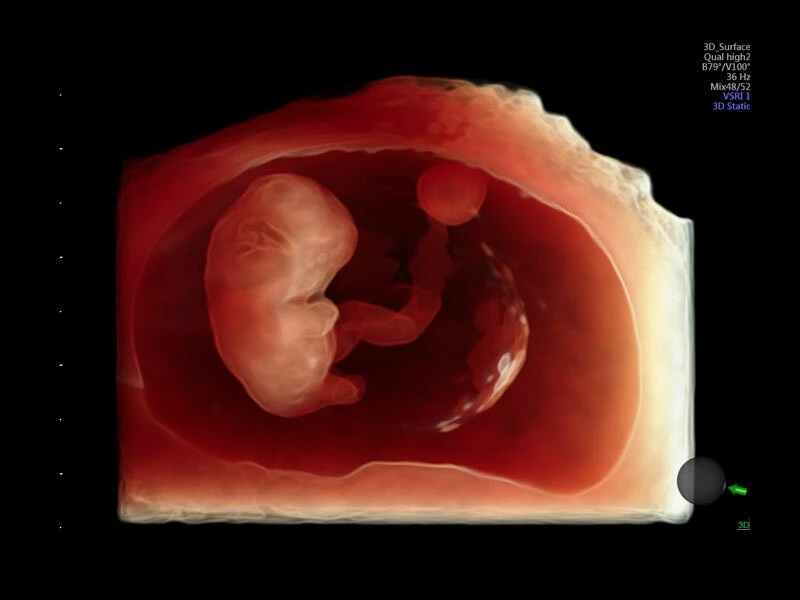

Объемное сканирование Voluson — 3D/4D вашей мечты

Объемное УЗИ на Voluson E10 — это не просто потрясающе красивая картинка, это ценный инструмент получения дополнительной информации при обследовании женщин.

Voluson E10 поддерживает инновационные технологии формирования изображений — HDlive Silhouette и HDlive Flow, которые позволяют увидеть мельчайшие детали. Алгоритм SonoRenderlive упрощает рабочий процесс и дает возможность реконструировать изображение поверхностей, определяя область перехода между тканью и жидкостью.

Инновационная технология визуализации HDlive обеспечивает получение реалистических изображений за счет эффекта объемного зрения, повышая достоверность клинической оценки. Теперь режим HDlive дополняют две новые функции:

- Технология HDlive Silhouette — задает разный уровень прозрачности, помогая выявлять контуры внутренних структур и точнее оценивать состояние плода в первом триместре.

- SonoRenderlive

- Улучшает объемную визуализацию за счет автоматического определения линии начала реконструкции при изображении поверхностей. При исследовании в режиме 4D функция SonoRenderlive непрерывно обновляет положение исходной линии с учетом движений плода.

- Позволяющая визуализировать плод в объеме стандартная программа HD-live с дополнительным приложением Hdlive Silhouette, включающим в себя режим «Силуэт», с помощью которого можно выделять границы тканей, контуры объектов. В этот же пакет входит и режим HDlive Flow, представляющий из себя источник света, перемещаемый и совместимый с режимом визуализации тока крови в объеме.

- Режим 3D SonoRenderLive – инновационная система, позволяющая определять четкие границы лица и конечностей плода в объеме, избавляясь при этом от лишних артефактов, шума и помех.